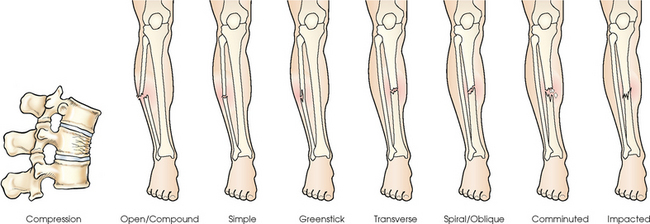

Common classifications of fractures are listed as follows and identified in Fig. 3-22:

Many fractures fall into more than one category. A fracture could be spiral, closed, and nondisplaced.